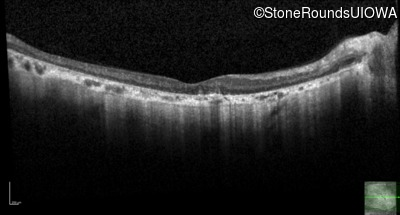

Optical Coherence Tomography - Left - 20/250 sc

Exemplar / OCT Stack